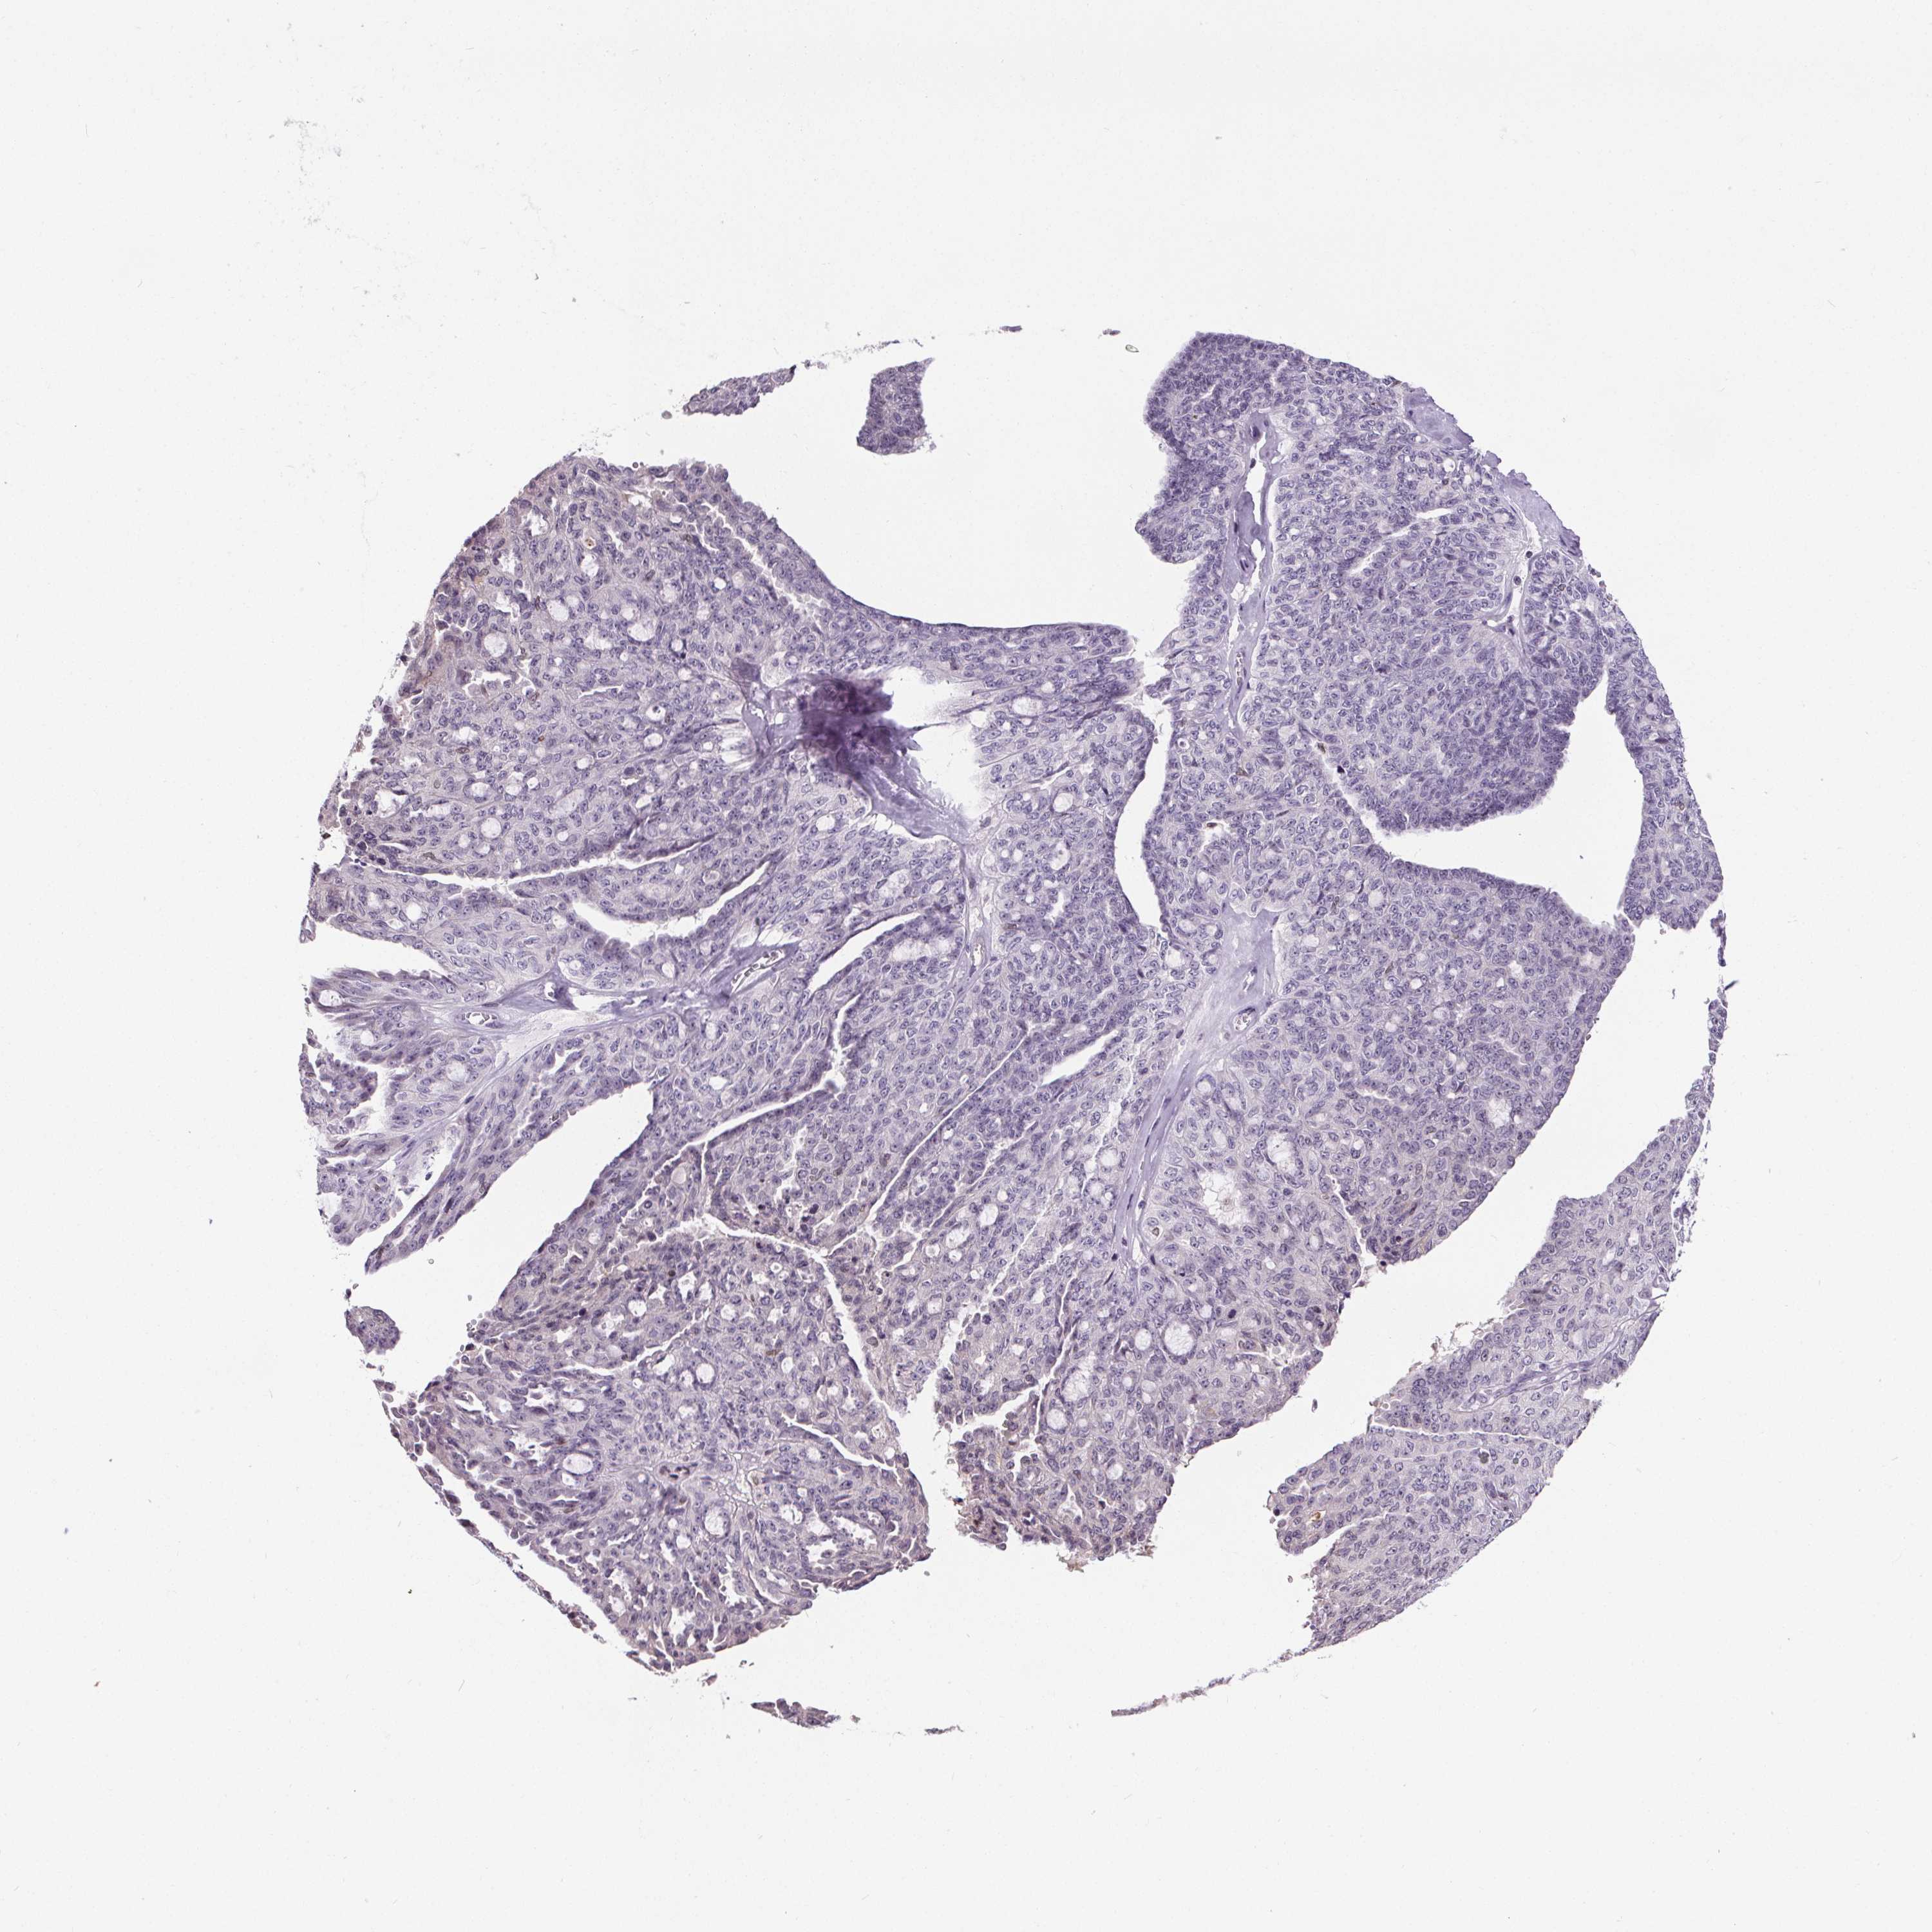

OVARIAN CANCER - Protein expressioni

A mouse-over function shows sample information and annotation data. Click on an image to view it in a full screen mode. Samples can be filtered based on level of antibody staining by selecting one or several of the following categories: high, medium, low and not detected. The assay and annotation is described here.

Note that samples used for immunohistochemistry by the Human Protein Atlas do not correspond to samples in the TCGA dataset.

Antibody stainingi

Antibody staining in the annotated cell types in the current human tissue is reported as not detected, low, medium, or high, based on conventional immunohistochemistry profiling in selected tissues. This score is based on the combination of the staining intensity and fraction of stained cells.

Each image is clickable and will lead to virtual microscopy that enables deeper exploration of all samples and also displays staining intensity scores, fraction scores and subcellular localization as well as patient and tissue information for each sample.

Antibody HPA066721

Cystadenocarcinoma, serous, NOS

Cystadenocarcinoma, mucinous, NOS

Carcinoma, endometroid